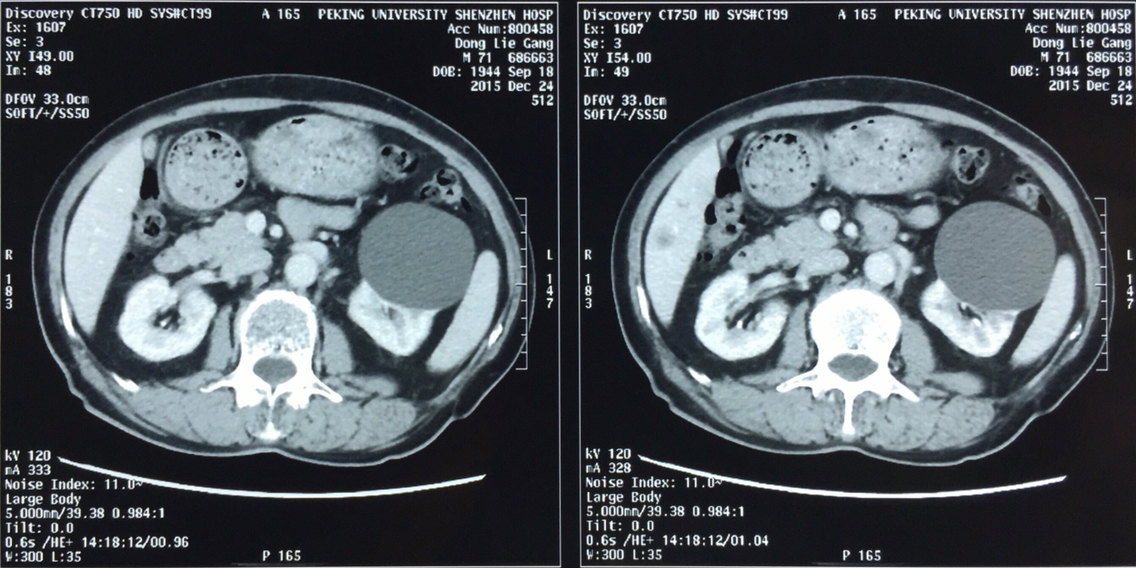

患者,男,72岁,ct显示双肾囊肿,左肾囊肿需要进行外科处理.